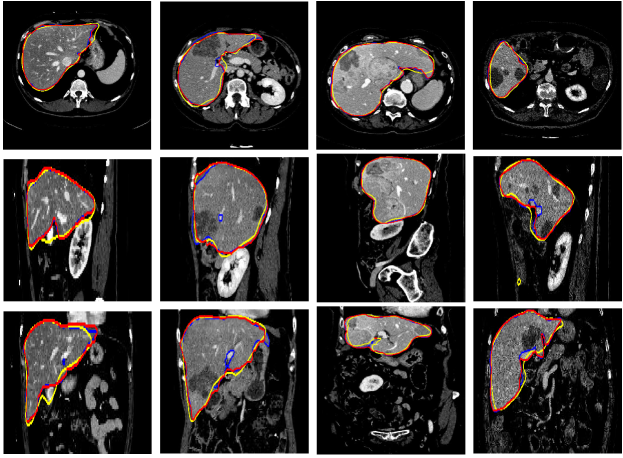

Refer to caption

Figure 7: 2D images of segmentation results of four challenging cases in axial, sagittal, and coronal planes with the ground truth in blue. The initial liver region generated by CNNs is in yellow and the final refined result is in red

Figure 8: 3D visual representation of livers segmented by our method on the same four cases as shown in Fig. 7. The first row shows the ground truth; the second and third rows present the surface distance error (mm) of 3D CNNs and the proposed segmentations with the ground truth

Figure 7 illustrates our segmentation and manual delineations for four challenging cases in coronal, sagittal, and axial planes. The initial liver region generated by 3D CNNs is in yellow, the final refined result is in red and the manual delineation is in blue. The first column shows a case with highly inhomogeneous appearances. The last three columns display three representative livers containing tumors. Particularly, some tumors locate on the boundary, which makes it more difficult to automatically delineate the accurate boundary. As can be seen, 3D CNNs can detect the most liver region and the refinement model can obtain a higher agreement with the ground truth. Figure 8 depicts the corresponding 3D visualization results of 3D CNNs and the proposed method for the cases shown in Fig. 7. The 3D visualization of errors is based on the MSD error between the segmentation result and the ground truth. As can been seen, the MSD errors of the 3D CNNs for the four cases (from left to right) are 22.1 mm, 12.6 mm, 62.6 mm and 74.5 mm, respectively, while the MSD errors of the proposed model are 17.0 mm, 11.2 mm, 22.1 mm and 15.3 mm, respectively. Obviously, the proposed approach can obtain lower errors in terms of MSD.

Figure 9: Four liver segmentation examples using the MICCAI-SLiver07 test data. The first row represents the segmentation results of the proposed method in axial plane. The second row shows the 3D visual representations of the final liver segmentation

To compare the performance of the proposed framework with state-of-the-art automatic segmentation methods, two tests are conducted on the MICCAI-Sliver07 test set and 3Dircadb database. In the first test, we submit the results on the MICCAI data to the MICCAI-Sliver07 challenge website and the evaluation is obtained by the organizers. Table 2 summarizes the corresponding results in terms of five metrics (VOE, RVD, ASD, RMSD, and MSD). The calculated mean ratios of VOE, RVD, ASD, RMSD, and MSD are 5.9%, 2.7%, 0.91%, 1.88 mm, and 18.94 mm, respectively. Figure 9 presents the results of four typical liver examples. Table 3 lists the comparative results of the proposed approach and the other eight fully automatic methods Li2015Automatic ; Al-ShaikhliYR15 ; ssm3 ; ssm4 ; Linguraru2011Liver ; Heimann2007A ; saddi based on MICCAI-Sliver07 test set. As can be seen, our method achieves a mean score of 77.8, outperforming most of the compared methods, such as Kainmu¨¨𝑢\ddot{u}ller (77.3), Wimmer (76.8), Linguraru (76.2), Heimann (67.6) and Kinda (64.1). In addition, the proposed method achieves the highest VOE and ASD scores.